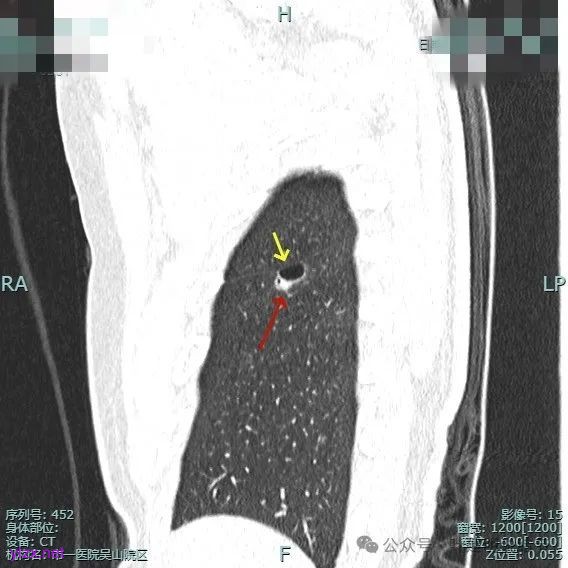

非薄层平扫上这个层面比较明显,似一囊腔,壁厚薄欠均匀。

薄层上看病灶贴着叶间裂与胸膜,此层囊壁薄,囊腔明显。

囊壁局部有增厚。

囊壁局部较厚,但囊壁内也是有小空泡的,病灶贴着胸膜。

病灶部分囊壁是混合磨玻璃成分的,整体轮廓较清。

边缘区也有偏实性成分,磨玻璃成分也还是明显的,有微小血管进入。

靶重建的影像上看,病灶的囊壁明显厚薄不均,有小血管进入,一侧的边似就是斜裂的样子。

囊壁有磨玻璃成分,边缘毛糙,有少许偏实性成分,仍有磨玻璃成分。

血管走向病灶,囊壁略不均。

此层见囊壁有较明显实性成分,血管进入明显。叶间裂侧平直。

混合密度,收缩力不明显,血管进入明显。

囊壁混合密度,整体轮廓清。

表面不平,血管进入,囊壁厚薄不均,紧贴叶间裂。

囊壁里面也有小空泡征。

混合密度但还是太致密,内壁毛糙不平。

病灶轮廓清楚,囊壁厚薄不均,贴着叶间裂与胸膜。